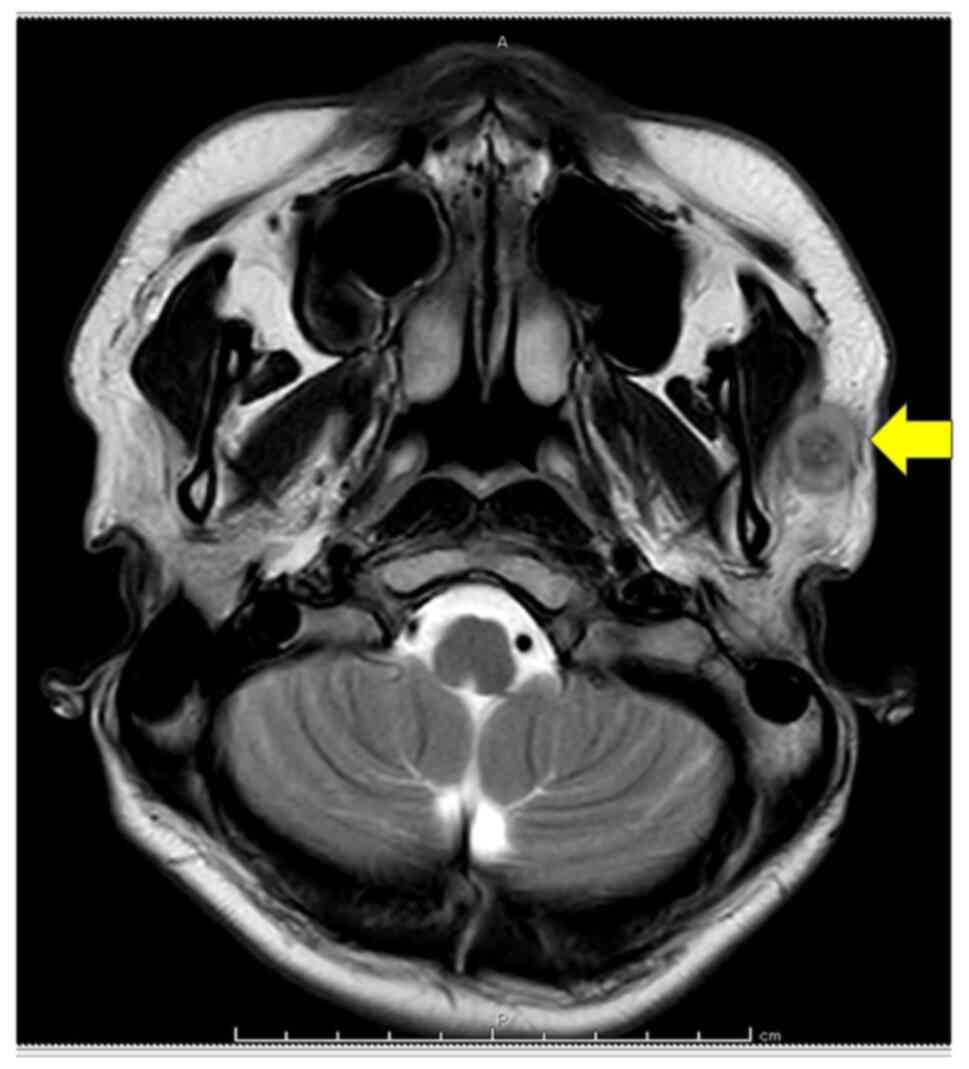

A 25-year-old male patient presented to Osaka Medical and Pharmaceutical University Hospital (Osaka, Japan) in June 2023 with symptoms of pain and firm left preauricular nodules that had persisted for six months. Magnetic resonance imaging of the neck showed a mass in the lower portion of the left parotid gland (Fig. 1). Following superficial parotidectomy and radiotherapy, no medication was administered and semiannual follow-up was continued. The patient has remained asymptomatic for one year and three months.

Figure 1

T2-weighted MRI showing a mass in the left parotid gland, indicated using an arrow.